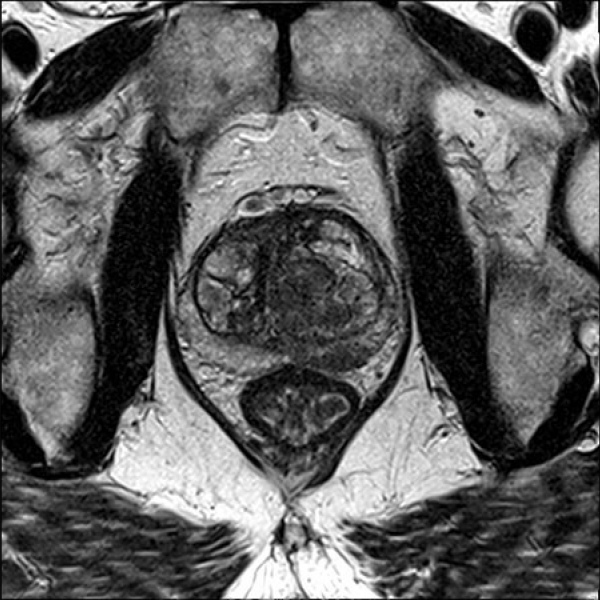

Resonancia nuclear magnetica multiparametrica contrastada de prostata. Idime

Se debe pagar aparte la espectroscopia y RM endorrectal con espiral endorrectal ($400.000)

INCLUYE MEDIO DE CONTRASTE Y SECUENCIA CONTRASTADA POR $209.000

INCLUYE TAMBIÉN ESPECTROSCOPIA, RESONANCIA ENDORRECTAL Y ESPIRAL ENDORRECTAL (ANTENA) POR $400.000

El medio de contraste es especial si el paciente tiene insuficiencia renal, es hipertenso, diabético, es pediátrico o tiene la creatinina elevada.